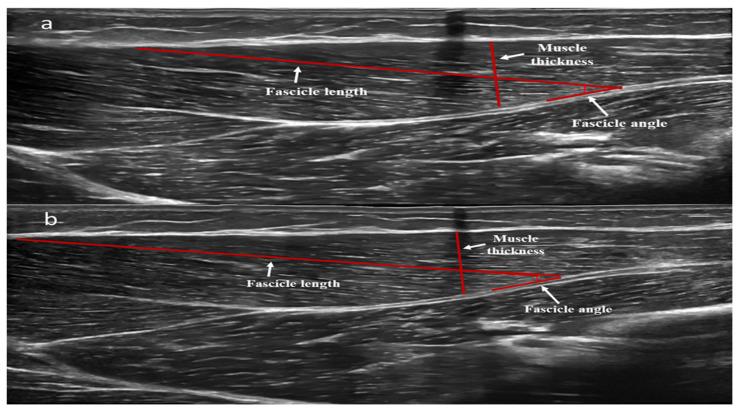

The aim of the present study was to investigate the effect of two long-term reduced concurrent training frequencies (incorporating power training for the upper and high-intensity interval aerobic training for the lower extremities), in which participants performed one training session every either 7 or 14 days, after 12 weeks of systematic concurrent training on upper extremities' muscle strength, power, and morphology in young females. After a 12-week concurrent resistance and aerobic training period, participants were assigned into three groups and performed either one training session every 7 days (G7), or once every 14 days (G14), or detraining (GD) for 12 weeks, followed by 12 additional weeks of detraining. Performance and muscle mass increased after the initial 12-week training period. After the reduced training frequency period, bench press 1-RM and aerobic power remained unchanged in G7 and decreased significantly in G14 (-5.9 ± 4.9%; -1.4 ± 4.5%). Muscle power and muscle thickness of the triceps branchii long head decreased significantly in G7 (-9.8 ± 7.7%; -0.9 ± 0.6%; respectively, < 0.05) and G14 (-10.9 ± 7.6%; -2.8 ± 2.7%, respectively, < 0.05), without significant differences between groups ( > 0.05). In conclusion, 12 weeks of systematic concurrent resistance (upper extremities) and aerobic training (lower extremities) induced significant improvements in upper extremities muscle power/strength and muscle architecture characteristics. Both reduced training frequencies led to significant reductions in power performance. Thus, performing one training session every 2 weeks for 3 months may preserve 90 to 95% of the muscle power/strength, aerobic power and 72% of muscle mass adaptations achieved with systematic concurrent training. However, greater preservations in the above parameters could be observed if the training frequency is one training session per week.

本研究的目的是调查两种长期降低的联合训练频率(包括上肢力量训练和下肢高强度间歇有氧训练)的效果,参与者在每7天或14天进行一次训练,在对年轻女性进行12周的系统联合训练后,观察其对上肢肌肉力量、功率和形态的影响。在进行了为期12周的抗阻和有氧联合训练期后,参与者被分为三组,分别每7天进行一次训练(G7组)、每14天进行一次训练(G14组)或停训12周(GD组),随后再进行12周的停训。在最初的12周训练期后,成绩和肌肉量有所增加。在训练频率降低期后,G7组的卧推1次最大重复量和有氧功率保持不变,G14组则显著下降(分别为-5.9±4.9%;-1.4±4.5%)。G7组(分别为-9.8±7.7%;-0.9±0.6%,P<0.05)和G14组(分别为-10.9±7.6%;-2.8±2.7%,P<0.05)肱三头肌长头的肌肉功率和肌肉厚度显著下降,组间无显著差异(P>0.05)。总之,12周的系统联合抗阻训练(上肢)和有氧训练(下肢)显著改善了上肢肌肉功率/力量和肌肉结构特征。两种降低的训练频率均导致功率表现显著下降。因此,每2周进行一次训练,持续3个月,可能保留系统联合训练所获得的90%至95%的肌肉功率/力量、有氧功率和72%的肌肉量适应性。然而,如果训练频率为每周一次训练课,则上述参数的保留情况会更好。